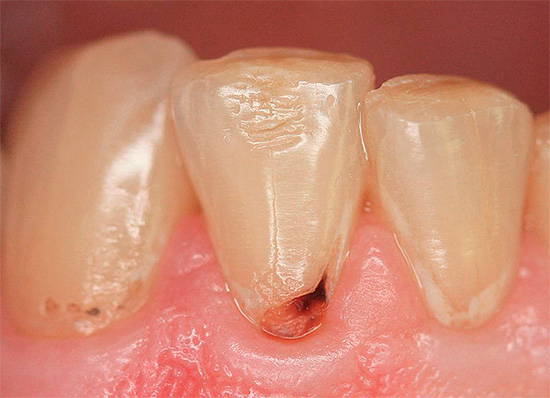

Se la malattia si sviluppa nella regione cervicale del dente, cioè in aree vicine alla gengiva, allora in questo caso stiamo parlando di carie cervicale. Una tale patologia ha anche un aspetto caratteristico: alla base, il dente sembra essere minato, a volte lungo l'intero perimetro, mentre la parte superiore della corona rimane spesso generalmente intatta.

Le fotografie seguenti mostrano alcuni esempi di carie cervicale: